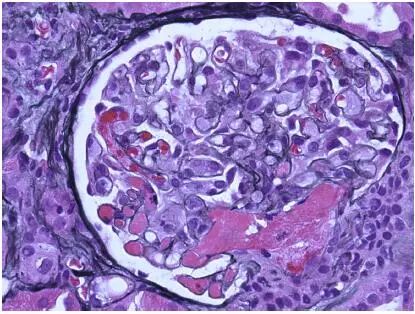

CNI肾毒性导致的血管收缩无形态学变化。急性CNI肾毒性特征包括:近端肾小管上皮细胞空泡化,大小一致;血管损伤,平滑肌细胞丢失;肌细胞胞浆空泡化;细胞坏死或凋亡退化。肌细胞损伤最终发展为局灶性结节性玻璃样变和透明样变,可延伸至小动脉和动脉血管壁整个中层。CNI肾毒性还可引起血栓性微血管病变(TMA),主要累及小动脉和肾小球毛细血管袢。慢性CNI毒性特征为:条状间质纤维化,肾小管萎缩。

图2 CNI肾毒性TMA,肾小球毛细血管袢和血管极(Jones 银染)